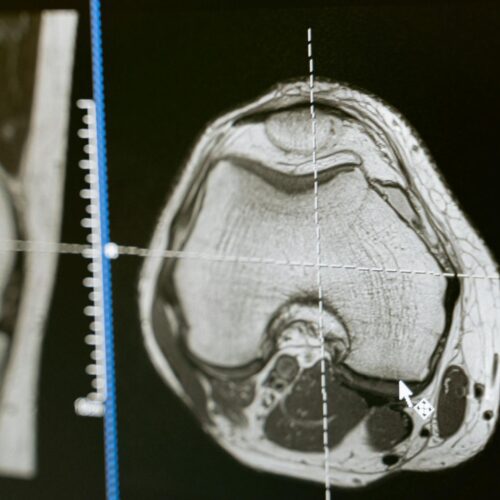

Radiologia